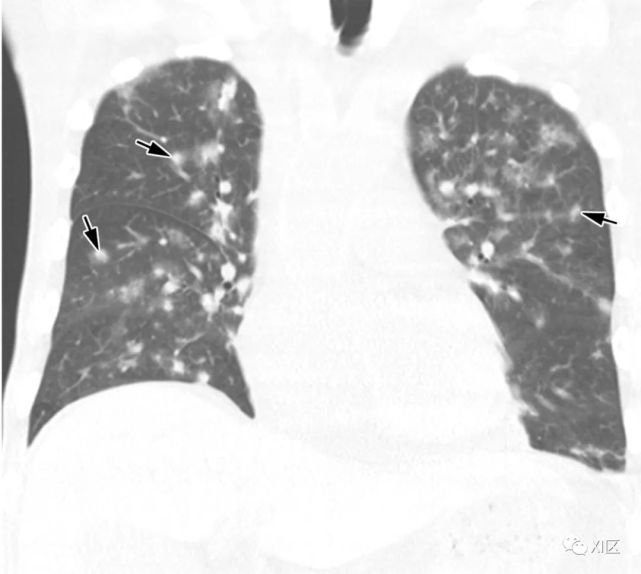

图13 63岁的男子,原发性中枢神经系统淋巴瘤化疗后合并发热,诊断为人博卡病毒肺炎

(上)胸部X线片显示两肺均弥漫性不规则斑块状实变(箭)和GGO。在同一天获得的轴位薄层(1mm)胸部CT图像显示,沿着支气管血管束和肺部周边区域出现不规则的斑块状实变(箭),支气管壁增厚,小叶间隔增厚 (箭头),伴有少量双侧胸腔积液(*)。

Koo H J , Lim S , Choe J , et al. Radiographic and CT Features of Viral Pneumonia[J]. Radiographics, 2018, 38(3):719-739.